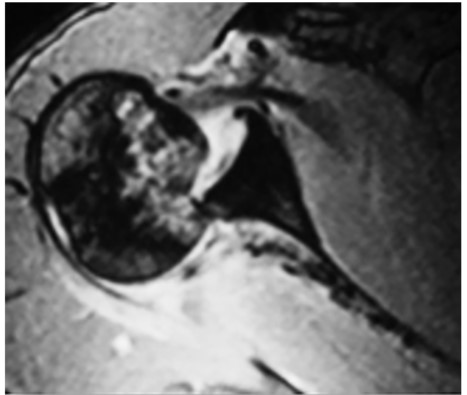

Lesiones de hombro, codo y muñeca

Los arqueros están más expuestos a los trastornos del hombro que otros jugadores de campo. Se desarrolló un programa, el hombro FIFA 11+, que se enfoca en la prevención de lesiones en el hombro en porteros de fútbol. Este programa tiene tres partes: ejercicios de calentamiento general, ejercicios para mejorar la fuerza y el equilibrio de los músculos del hombro, el codo, la muñeca y los dedos, y ejercicios avanzados para la estabilidad central y el control muscular. Se eligieron los ejercicios en base a estudios de electromiografía. Un tercio de las lesiones de hombro (28%) sufridas por futbolistas profesionales son graves debido a que se detiene durante más de 28 días [8]. Cuando hablamos de luxación glenohumeral (Figura 5), se trata de una lesión grave que en el 84% de los casos compromete el labrum, asociada al manguito rotador en un 8%. El mecanismo de lesión puede ser directo o indirecto (más frecuente). Esta afección para el arquero de fútbol, como otros deportes (básquet, vóley, handbol, lucha, rugby), significa un alto riesgo para retornar a la competencia en la misma temporada. El tratamiento indicado es la reparación artroscópica en el primer episodio debido a su alto porcentaje de recidiva (80 a 94%). Es común encontrarnos con lesiones de SLAP relacionado con los lanzamientos con el miembro superior. Generalmente resueltas en forma incruenta.                                                                                                                             Las epifisiolisis de radio se producen comúnmente en niños o adolescentes cuando intentan bloquear un disparo directo con balones de tamaño del adulto.  Por lo tanto, jugar con pelotas apropiadas para la edad, trabajar la técnica del bloqueo y al caer.

Con respecto a la luxación acromioclavicular (Figura 6), su tratamiento generalmente es conservador, solo son quirúrgicas cuando hay dolor crónico y gran inestabilidad con disquinesia escapular. En caso de optar por un tratamiento quirúrgico en lesión aguda, sugerimos usar injerto biológico según técnica y técnica de las 5 hebras.

Si bien la incidencia general de lesiones en el hombro y el codo en jugadores de fútbol fue de 2,7/10.000, la incidencia entre los porteros fue 4,6 veces mayor (8,3 frente a 1,8/10.000). Las mujeres arqueras fueron más afectadas, con incidentes de lesiones 7,7 veces más altos que las jugadoras de campo, y 1,9 veces más altas que los porteros varones [9].

Las lesiones óseas más comunes de codo son: fractura cúpula radial (Figura 6) por caída con la mano con codo extendido (con o sin luxación), apófisis coronoides y fractura de Monteggia. La lesión ligamentosa más común es la del ligamento lateral interno por bloquear el balón con la cara cubital de la mano con el miembro superior en extensión y supinación o al cargar el peso al apoyar la mano con brazo en extensión. Las bursitis olecraneanas se producen por trauma directo.

Figura 5. Luxación escápulo-humeral

Figura 6. Fractura de la cabeza radial